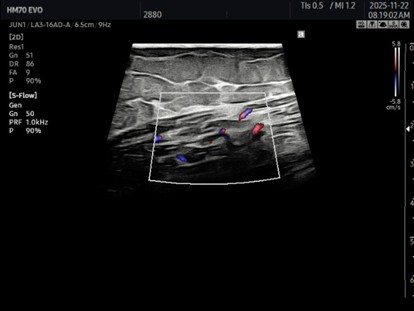

膝関節完全屈曲(+)、エコーにて

点状出血がみられ大内転筋の

肉離れではなくハンター管の剥離が

起きていたことが分かった。